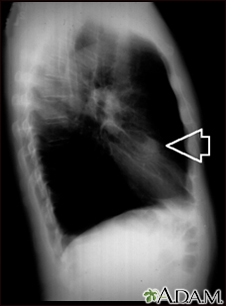

Lung nodule, right middle lobe - chest x-ray